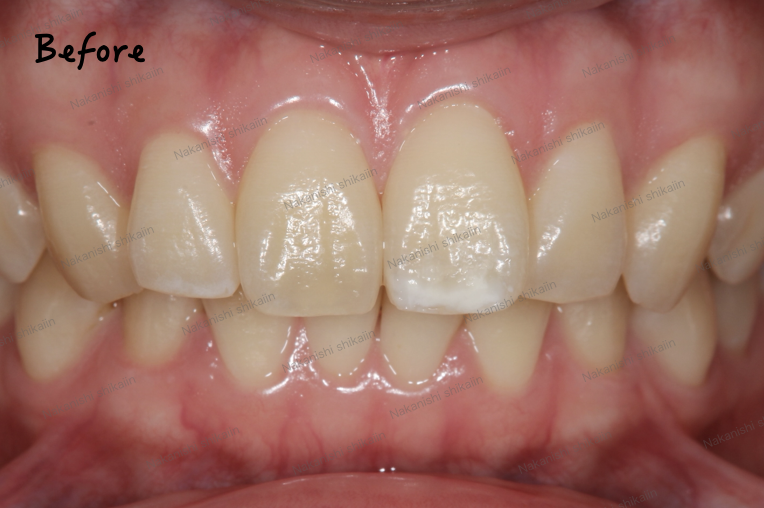

前歯のセラミックス審美治療の実際のご紹介です。

写真のように、変色している歯と、斜めに捻じれている歯があります。見た目の雰囲気が気になるところです。

歯の捻じれについては矯正治療が視野に入ります。矯正治療といっても治療期間や費用がネックになるので、そのあたりが患者様と要相談となります。今回はともに神経が無い歯であったので、被せ物にして見た目を改善しようというお話になりました。

神経がない歯は強度も落ちる言われています。被せ物にすることで一定の強度を担保できるのも利点です。もちろん歯が十分に残っている場合は被せ物にする必要はありませんが、最終的には患者様と要相談となります。今回は見た目の改善を目的として、被せ物を作成するために歯を一回り削り、土台という形にしています。

被せ物が入った状態です。見た目がかなり改善し、周りと比較しても違和感がない状態です。

ニコッとした時も見た目が綺麗で揃っているので、違和感がなく綺麗な状態です。